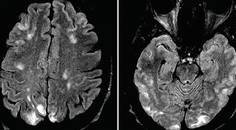

Case Report: New-Onset Headache With Tinnitus and Orthostatic Dizziness

Ryan P. CoburnRyan P. Coburn - Stroke